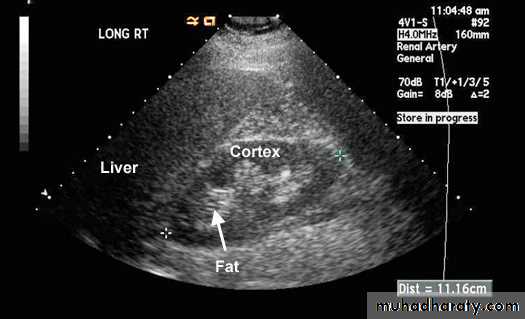

Normal Kidney; Normal kidney measures between 10.5 to 12.5 cms. Cortex is about 2.5 cms and has the same kind of echoes as liver. Medulla is hypoechoic and appears dark.

Chronic Renal Failure; Kidneys are smaller than normal. Surface may be irregular. Cortex is thinned and is hyperechoic than liver due to scar tissue. Medulla is hypoechoic and appears dark.